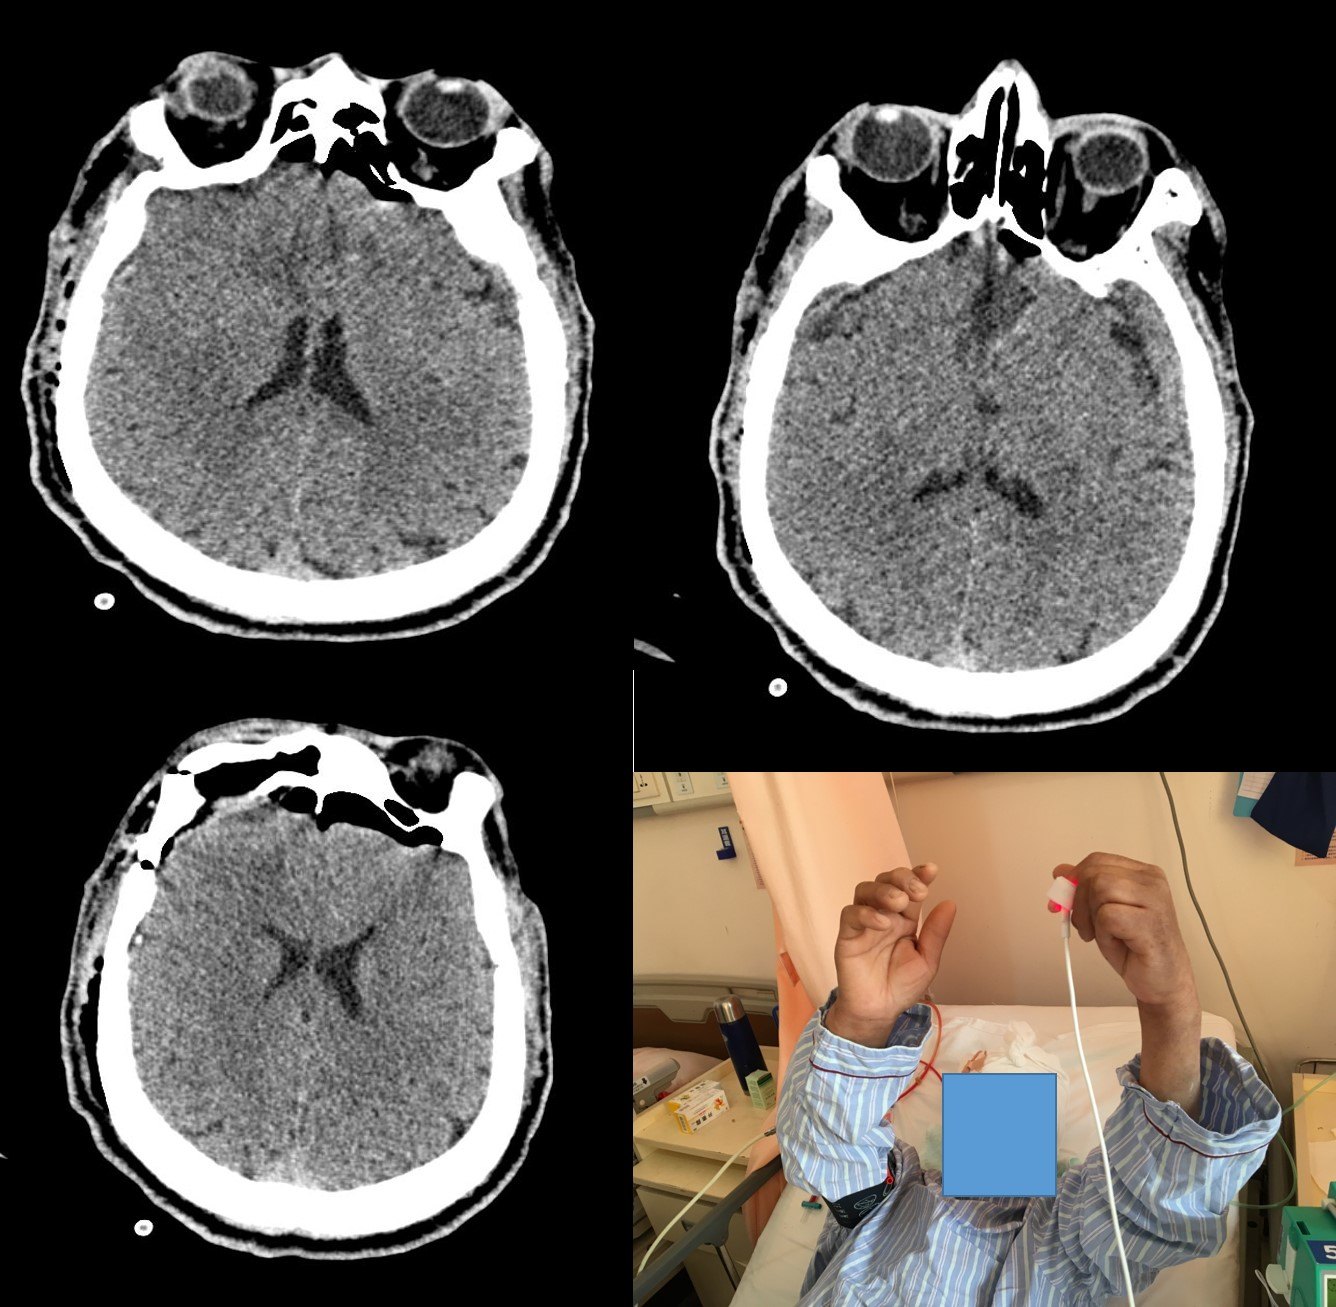

术后即刻CT示:术区干净,无渗血及水肿表现,中线结构居中。

术后第一天患者清醒,对答流利,视物可,四肢自主活动。